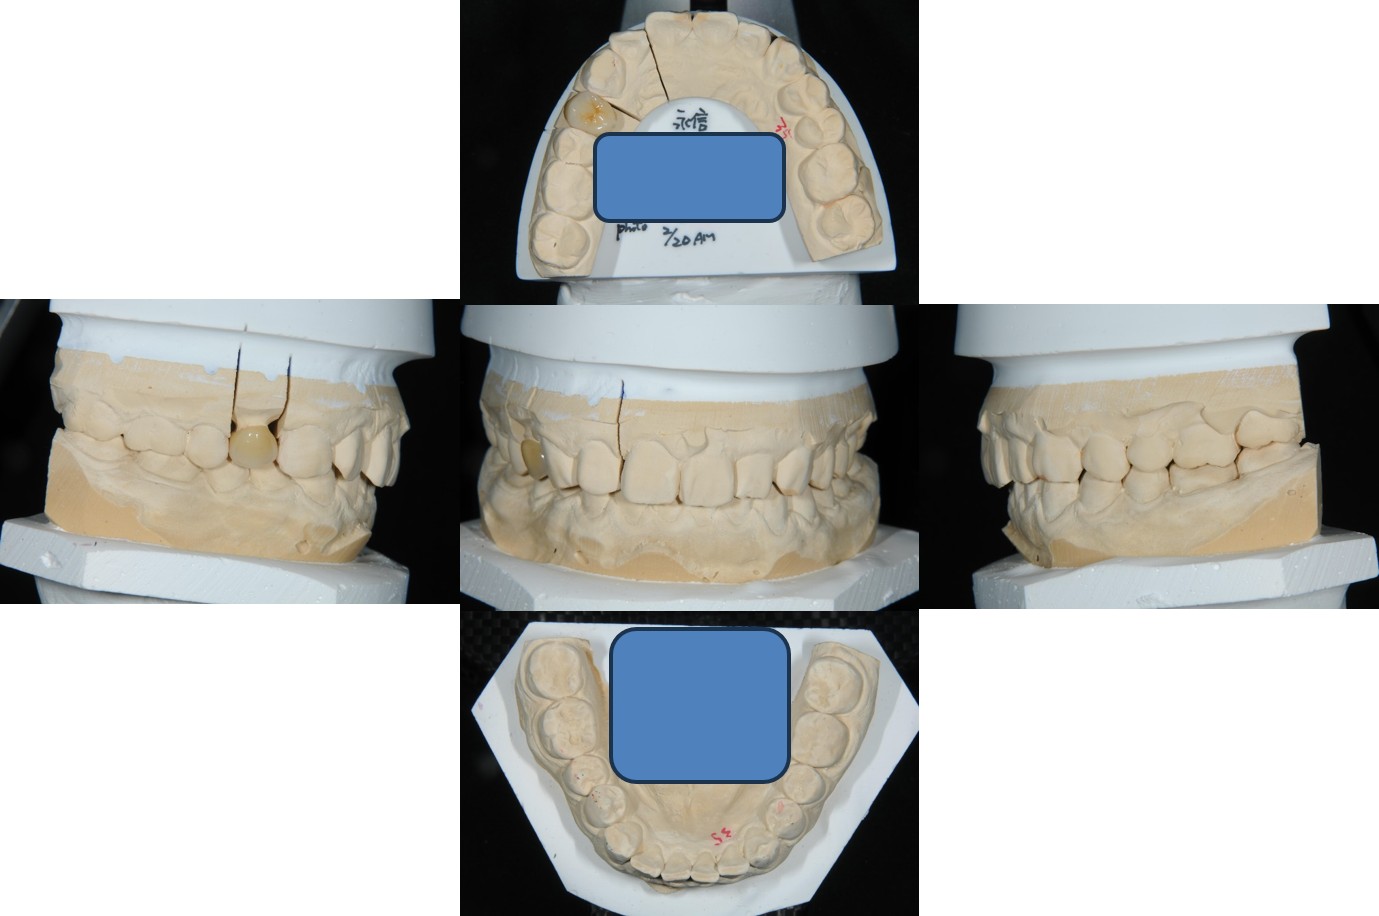

上面弓、上咬合器

技師於咬合器製作全瓷冠